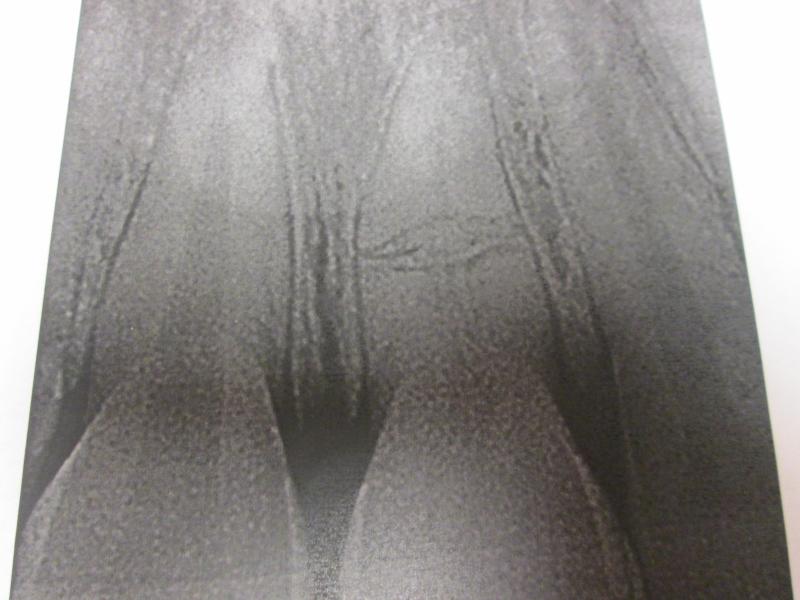

"DR. JET'S MISSION IS TO PERFORM  ROOT CANALS FOR A REDUCED FEE USING THE LATEST TECHNOLOGY  AND TECHNIQUES TO SERVICE THE MANY PEOPLE WHO ARE UNINSURED OR UNDER-INSURED GIVING EVERYONE AN OPPORTUNITY TO SAVE THEIR TOOTH!"

**PLEASE BE AWARE THAT  A ROOT CANAL IS AN ATTEMPT TO SAVE YOUR ALREADY DAMAGED TOOTH.  THERE IS NO GUARANTEE THAT ANY TOOTH CAN BE SAVED BUT DR JET WILL DO HIS BEST TO HELP YOU. THE OTHER OPTION IS TO EXTRACT YOUR TOOTH